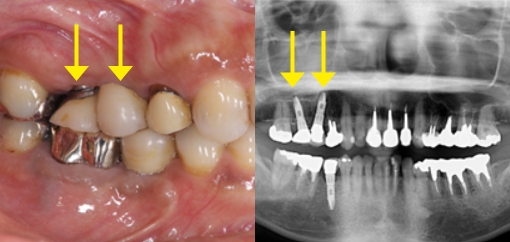

埋入位置(インプラントポジション)の大切さ

適当に骨がある位置にインプラントを埋入してしまうと、その上に接続される歯冠部の形態がおかしくなり、歯肉の炎症やかみ合せの不良が発生します。この状態からリカバリーするためには、インプラントを撤去したうえで失った骨や歯茎を再生させるなど、多くの時間と費用、肉体的苦痛が伴ってしまいます。

インプラントの埋入方向悪いため歯冠部の形態がおかしくインプラント周囲炎を起こしている